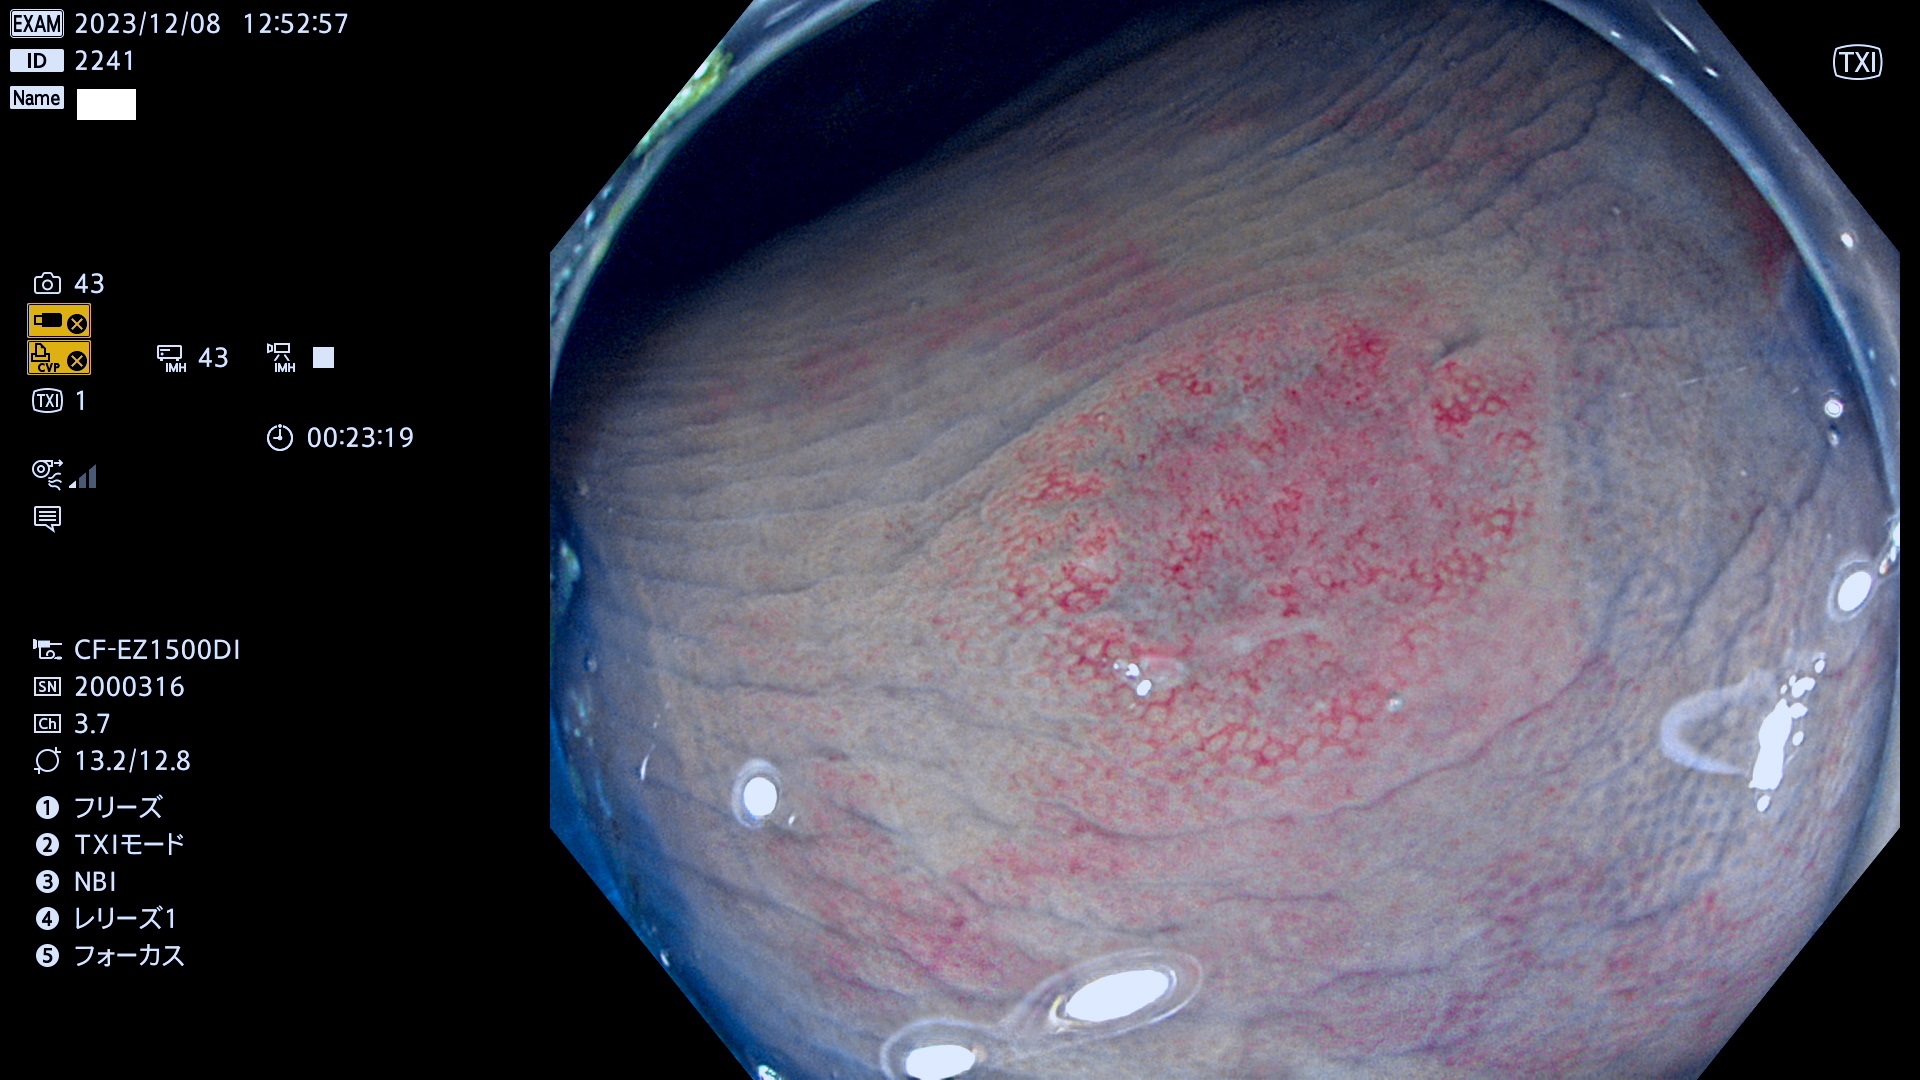

表面型腺腫(Flat Adenoma)の中で、完全に平坦な物をUb、陥凹している物をUcと呼びます。平坦隆起型(Ua)よりも、発見が難しく危険な病変です。このタイプは「内視鏡後・大腸癌の重要犯人」であり、この発見率は「腺腫発見率」よりも、重要な意味があります。

毎週の検査(木・金・土・日)に発見されたUb、Uc型・腺腫を、その週の日曜の夜にUPし1週間、提示します。

抽出の対象期間 2023年12月7日(木)〜12月10(日)の4日間(48件の検査)12件